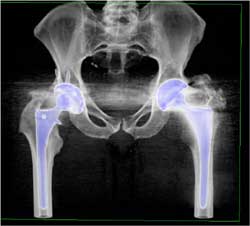

Diagnosis

Acute Rectus Bleed